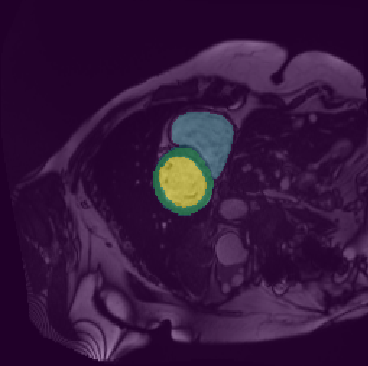

In this paper, we aim to improve the performance of semantic image segmentation in a semi-supervised setting in which training is effectuated with a reduced set of annotated images and additional non-annotated images. We present a method based on an ensemble of deep segmentation models. Each model is trained on a subset of the annotated data, and uses the non-annotated images to exchange information with the other models, similar to co-training. Even if each model learns on the same non-annotated images, diversity is preserved with the use of adversarial samples. Our results show that this ability to simultaneously train models, which exchange knowledge while preserving diversity, leads to state-of-the-art results on two challenging medical image datasets.